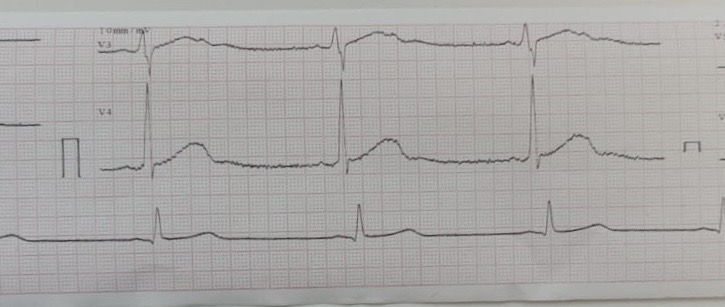

Блокированная ЭС на фоне рубцов

Вложения:

IMG_8846.jpg

IMG_8846.jpg [ 111.27 KiB | Просмотров: 23155 ]

IMG_8847.jpg

IMG_8847.jpg [ 108.77 KiB | Просмотров: 23155 ]